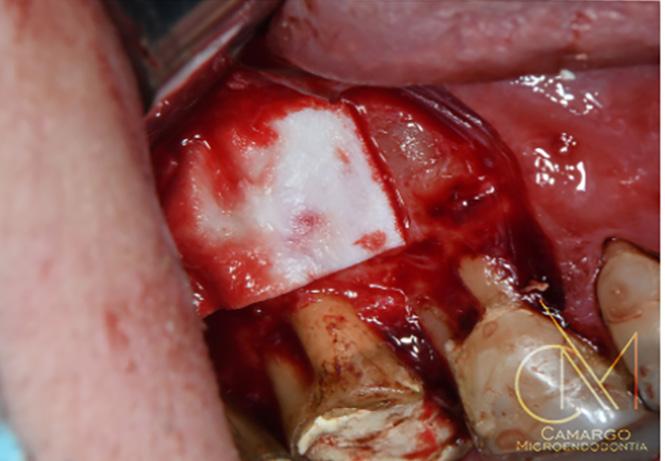

Los dientes anteriores (n.º 13 23) se feru lizaron con una férula periodontal Rib bond, y la oclusión se ajustó a un contac to ligero. Se elevó un colgajo de espesor total, y el defecto se descontaminó con una combinación de láser de CO2 de 9,3 micras y EDTA al 24 %. Después de la descontaminación confirmamos un de fecto de una pared con una bolsa perio dontal intraósea de 7 mm. Injertamos el defecto con Geistlich Bio‑Oss® Collagen, que tiene una excelente capacidad para actuar como andamiaje y resulta muy útil en esta indicación.1 Después cubrimos el injerto óseo con L PRF™ para una mejor respuesta angiogénica de los tejidos.

G Radiografía periapical a los 12 meses del seguimiento. | H Hueso nuevo alrededor de los dientes 11 y 12 en la reentrada.| I Resultado final. cumplimiento del paciente, es posible re parar dientes con un pronóstico de poco favorable a insalvable. 2 4

Dientes funcionales y estéticos después de salvarlos

La paciente fue sometida a un seguimien to de 12 meses, donde se puso especial atención a la regularidad de las visitas y a la higiene oral. Al año del seguimiento y en la reentrada para mejorar el perfil del teji do blando, confirmamos que el defecto se había rellenado por completo con hueso nuevo con una adaptación estrecha a los

dientes 11 y 12. La radiografía periapical tomada en el momento confirmó las ob servaciones clínicas. Este caso destaca la importancia de realizar los diagnósticos actuales en base a los biomateriales

| A Antes del tratamiento ortodóncico. | B CBCT periapical antes del tratamiento periodontal. | C Dientes (13 y 23) ferulizados. | D Bolsa intraósea de 7 mm después de abrir el colgajo. | E Geistlich Bio-Oss® Collagen rellenando el defecto. | F Membrana L-PRF™ bioactiva cubriendo el injerto óseo. |

| A Tomografía computarizada de haz cónico (CBCT) coronal o sagital que muestra la proximidad de la lesión periapical y el seno maxilar. | B Oclusión correcta antes del tratamiento. | C Plantilla quirúrgica 3D para guiar el acceso. | D Osteotomía con el Piezotome Cube (Acteon, EE. UU.) usando la punta SL1 después de elevar el colgajo. | D Osteotomía con el Piezotome Cube (Acteon, EE. UU.) usando la punta SL2 | F Preparación retrógrada sobre la raíz mesiovestibular con una punta Berutti (EMS, Suiza) e irrigación salina. | G Biocemento Bio C Repair (Angelus, Brasil) aplicado en el conducto mesiovestibular. | H Fotografía con el microespejo de 3 mm para comprobar la obturación retrógrada en la raíz distovestibular del segundo molar derecho superior. | I Geistlich Bio-Oss® Small 0,5 g. (Geistlich Pharma AG, Suiza) en el sitio quirúrgico. | J Cavidad quirúrgica rellenada con Geistlich Bio-Oss® Small. | K Membrana Geistlich Bio-Gide® 25 × 25 mm usada para cubrir el injerto. | L Radiografía final después de la cirugía.